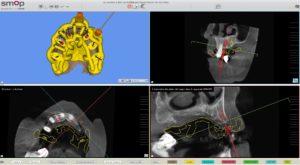

Un cone beam et une prise d’empreinte optique ont été nécessaire pour réaliser la planification implantaire du cas.

Il a été prévu de poser 6 implants au Maxillaire et 4 implants à la mandibule .

2 guides SMOP ont été imprimé, appuis dentaires, muqueux + fixation par clavettes.

Le guide SMOP est numérisé en place avec les transferts, cela nous permet de retrouver l’occlusion.